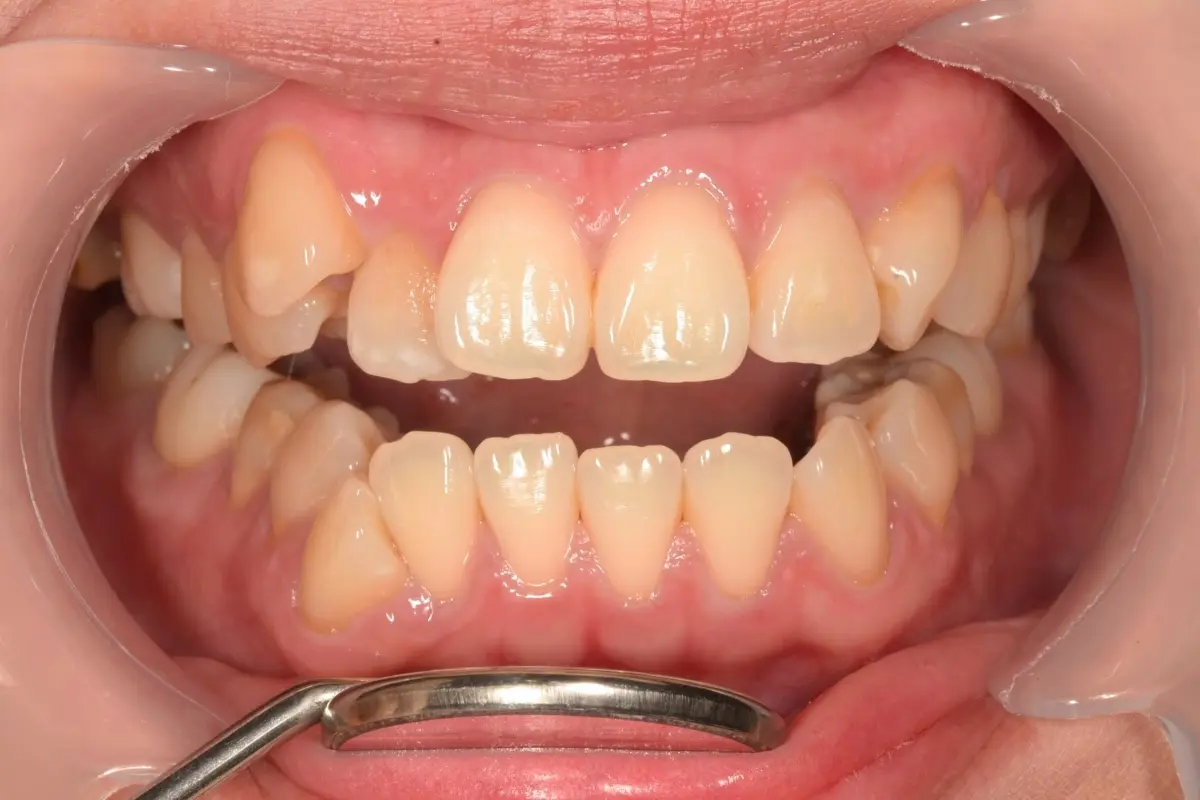

牙周治療

主治醫師

• 鍾國耀

治療時間

三次療程

主訴

牙齦紅腫出血、牙縫容易塞食物